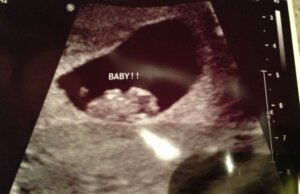

Raskauden alkuvaiheessa alkio on hyvin lähellä istukkaa. Tällöin on tärkeintä tarkastella kirkasta aluetta ultraäänikuvassa. Nukkalisäkkeen sijainti riippuu paljon siitä, millainen ultraäänitutkimus odottavalle äidille on tehty. Ultraäänitutkimus voidaan suorittaa emättimen kautta tai vatsanpeitteiden päältä.